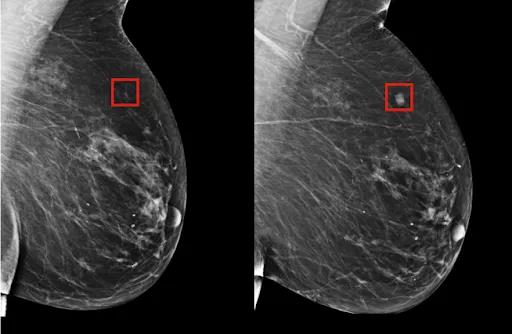

簡言之,乳腺鉬靶是利用X線成像,對小鈣化敏感,可以發(fā)現(xiàn)臨床摸不到的乳腺腫塊,尤其是對于大乳房和脂肪型乳房,其診斷性可高達95%。也只有憑借乳腺鉬靶檢查,才能對于以少許微小鈣化為表現(xiàn)的T0期乳腺癌被早期發(fā)現(xiàn)和診斷,這在沒有任何乳房問題以及癥狀的女性中尤為適用。

但由于乳腺鉬靶是二維成像,腺體致密的時候,會出現(xiàn)造成漏診和誤診的可能。比如,對于在乳房表面附近發(fā)現(xiàn)的腫塊,容易受到重疊組織干擾,就會出現(xiàn)漏診情況。但在某些情況下,乳房超聲檢查比鉬靶檢查能夠更好地檢測乳腺癌。超聲檢查對年輕女性、致密型乳腺均較理想,可以更好的檢測到這些遺漏。